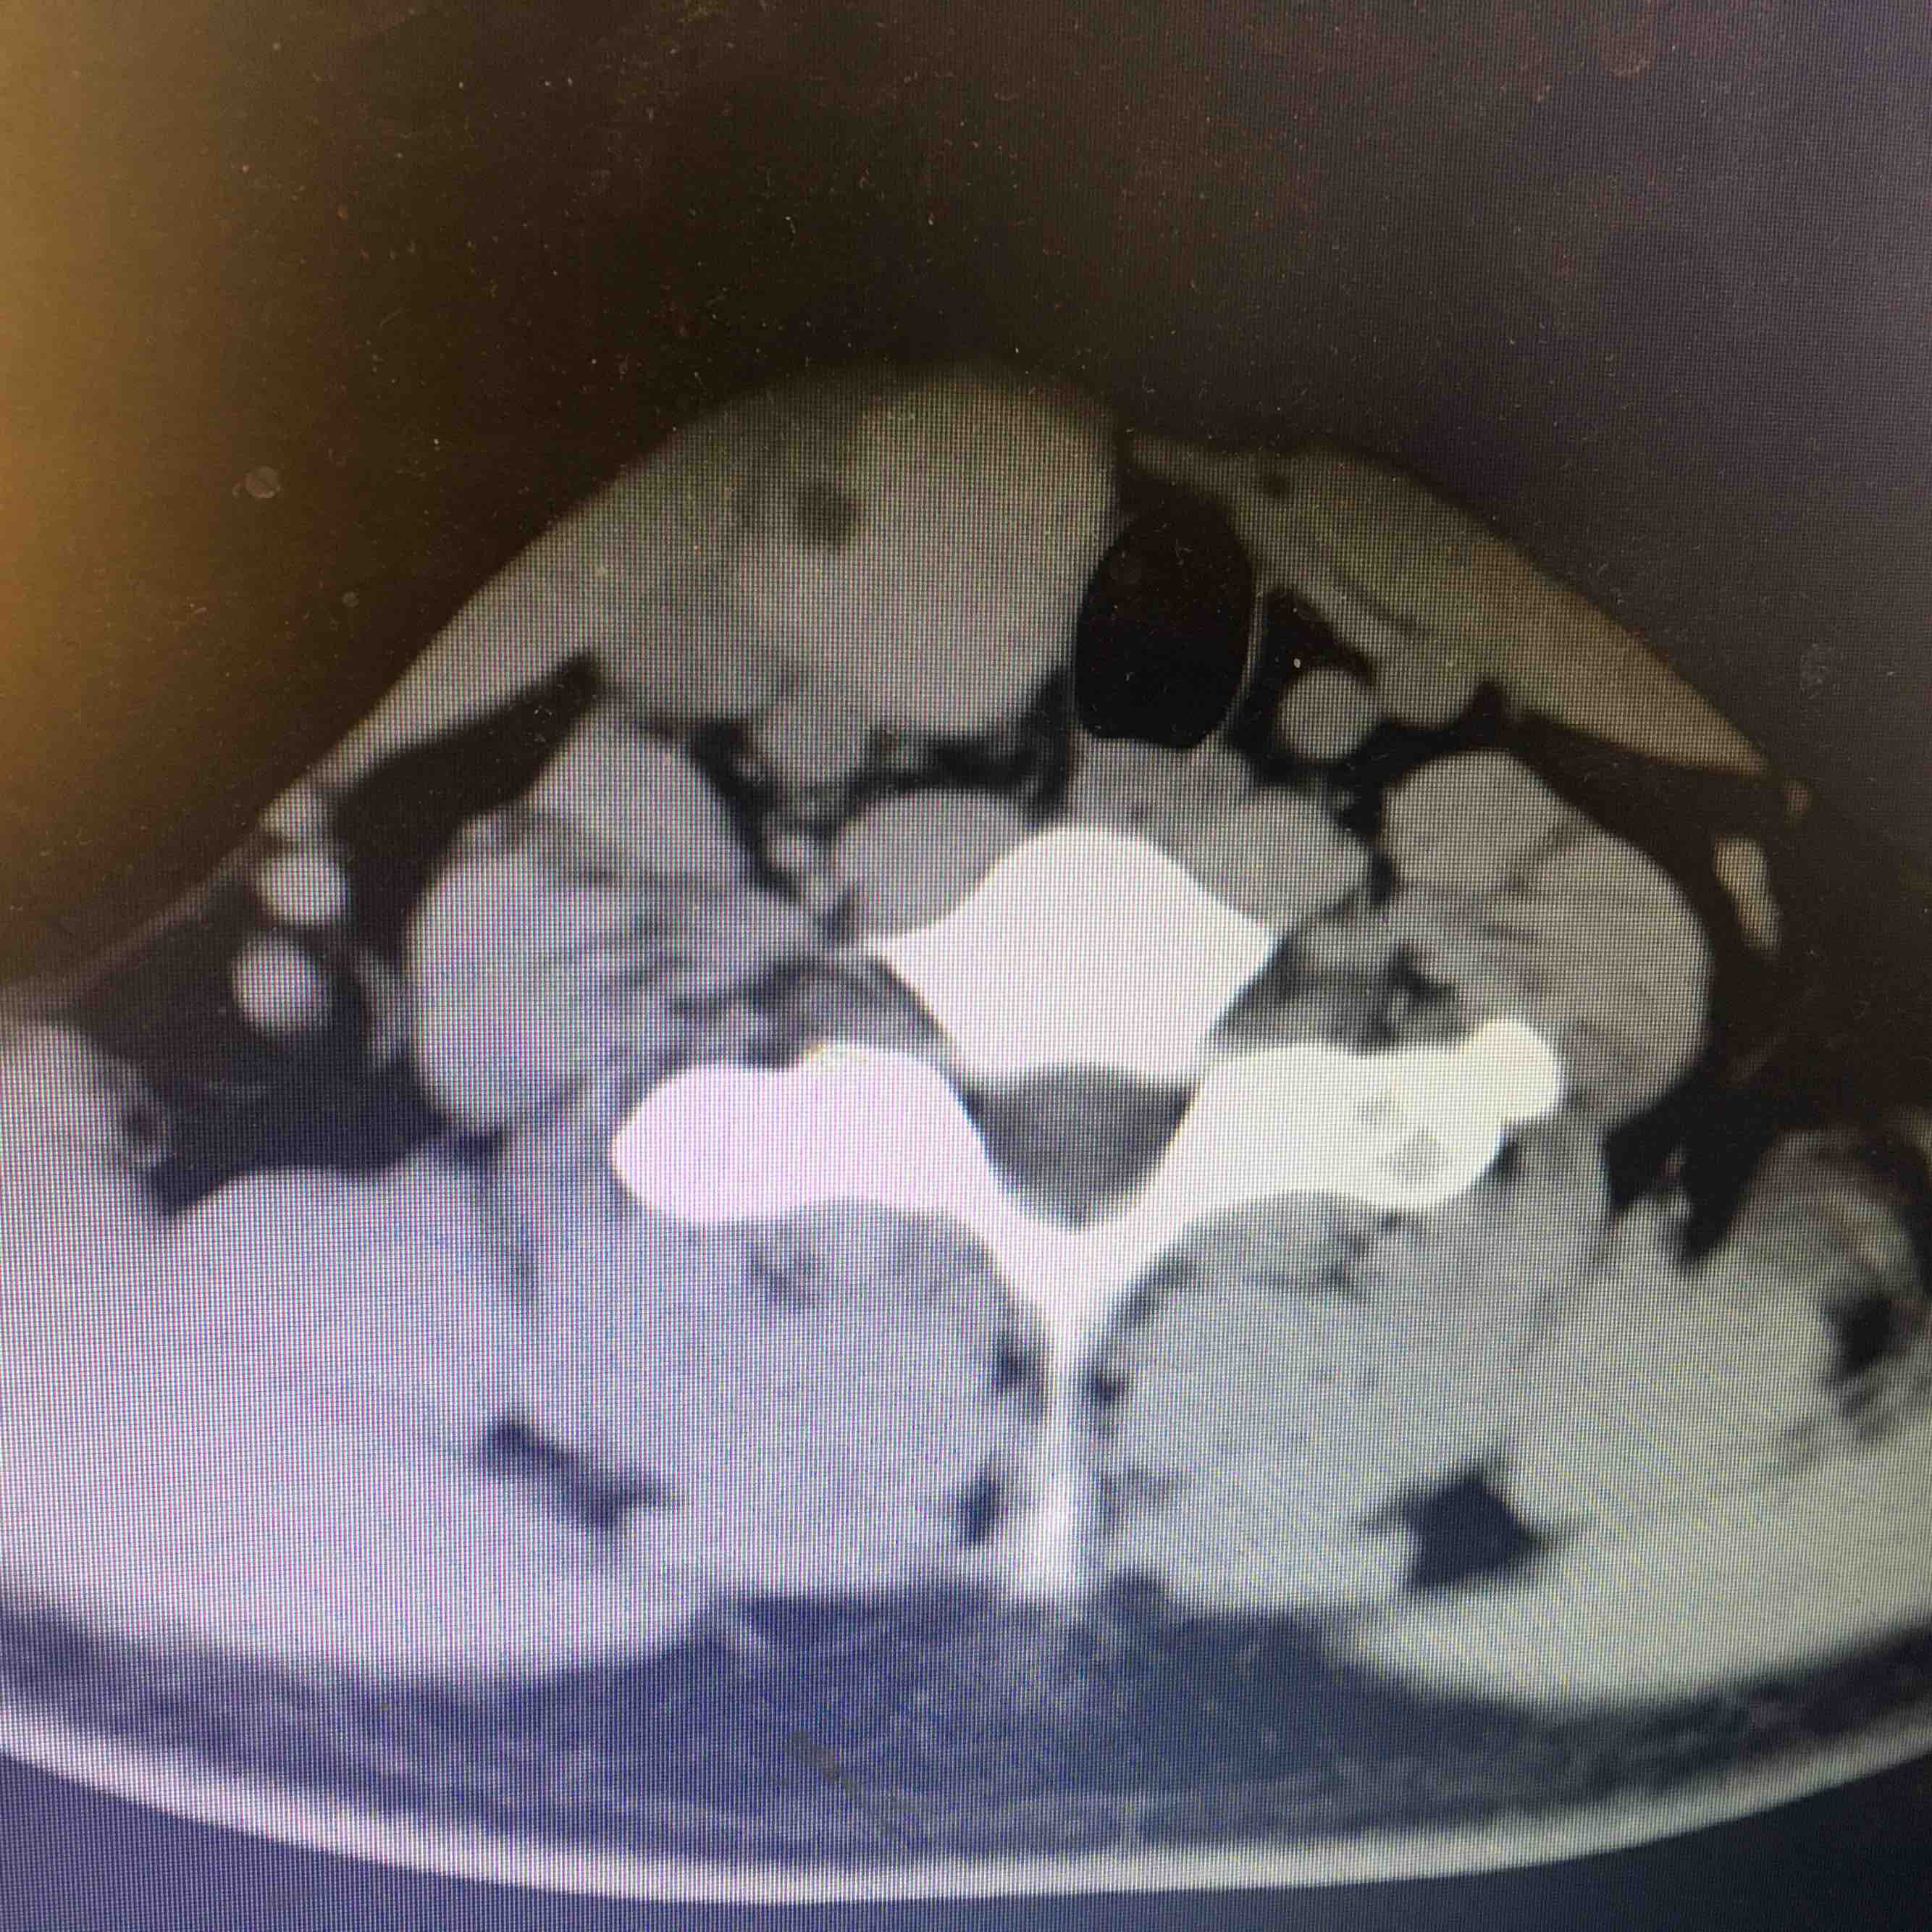

查体  颈软,气管向左侧移位,甲状腺右侧叶可触及一大小约3cm✖️3cm肿物,质韧,表面光滑,边界清晰,可随吞咽上下移动,局部压痛阴性。辅助检查  甲免五项正常。甲状腺彩超示甲状腺右侧叶囊实性病变,甲状腺左侧叶显示不出,考虑缩小。颈部CT示右侧甲状腺占位置病变,建议进一步检查,左侧及峡部甲状腺缺如,请结合临床。

诊断 甲状腺右侧叶肿物 性质待查      甲状腺左侧叶峡部缺如处理 患者要求赴上级医院进一步检查和治疗

先天性甲状腺一侧叶缺如非常少见,需要进一步完善相关检查,了解有无异位甲状腺组织。